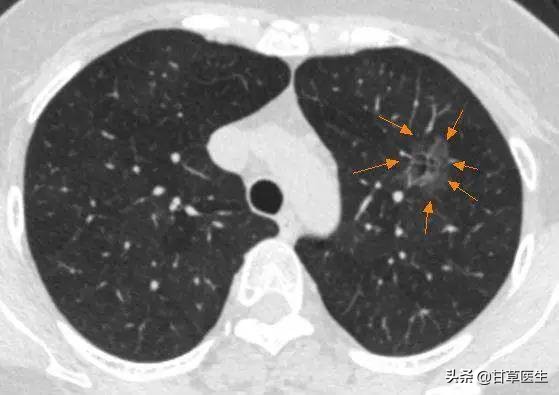

磨玻璃结节

磨玻璃结节示意图,来源:上海市肺科医院陈谢冬